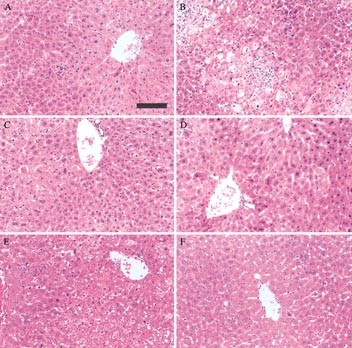

Figure 8

Effect of AxCA-mMIFS or AxCA-mMIFAS on histologic changes in the liver of mice treated with BCG and LPS. A, BCG alone; B, BCG/LPS; C, BCG/AxCA-mMIFS; D, BCG/AxCA-mMIFAS; E, BCG/LPS/AxCA-MIFS; F, BCG/LPS/AxCA-MIFAS. The arrow indicates the marked infiltration of mononuclear cells. The scale bar in A indicates 400 ÎĽm (original magnification, Ă—50)